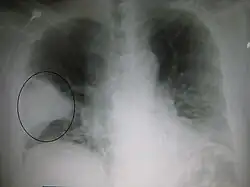

A black and white X-ray picture showing a triangle white area on the left side. A circle highlights the area.

A chest X-ray showing a very prominent wedge-shape bacterial pneumonia in the right lung